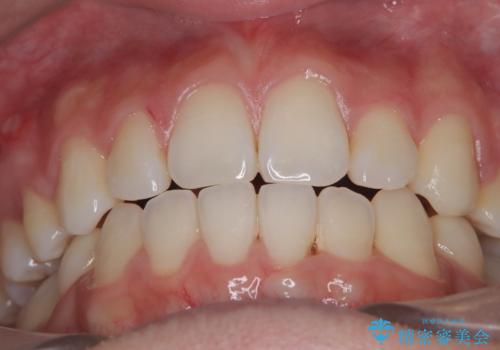

上下左右の第一小臼歯を抜歯し、クリアブラケット(白い装置)とメタルワイヤーを使用して矯正を開始。初期には犬歯のアーチ内への整列を優先し、中盤からは前歯と奥歯の咬合関係の調整を進めました。審美性に優れた装置を使用したことで、治療中も目立ちにくく、見た目へのストレスが少ない点も評価されています。全体の治療は1年半で完了し、見た目・噛み合わせともに大きく改善。患者本人も「短期間でここまで変わるとは思わなかった」と満足されていました。